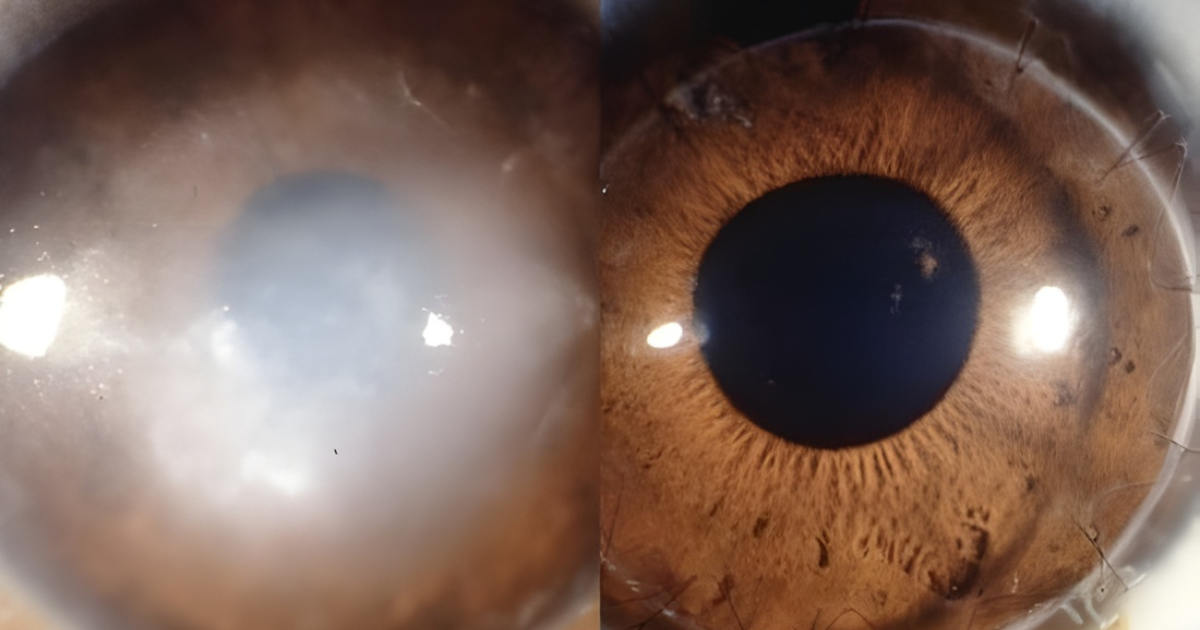

1. DMRI seca (ou atrófica)

É a forma mais comum, representando cerca de 85–90% dos casos. Ocorre quando há um desgaste progressivo das células da mácula (atrofia), resultando em visão borrada e perda gradual da nitidez.

2. DMRI úmida (ou exsudativa)

É a forma menos comum, porém mais agressiva. Caracteriza-se pelo surgimento de vasos sanguíneos anormais sob a retina (neovascularização). Esses vasos são frágeis e costumam vazar sangue e líquido, causando perda rápida da visão central.